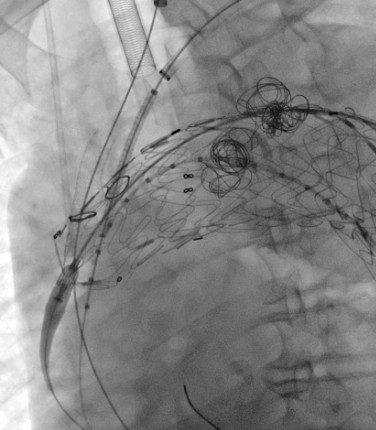

穿刺股動(dòng)脈、切開頸動(dòng)脈、肱動(dòng)脈建立入路,超選內(nèi)漏口、栓塞瘤腔,體外預(yù)開窗、重建弓上動(dòng)脈......血管外科兩組人馬同時(shí)開工,有條不紊。在麻醉科林芩主任團(tuán)隊(duì)的密切配合下,一系列步驟緊張有序地進(jìn)行著。手術(shù)持續(xù)了4個(gè)多小時(shí),當(dāng)最終的造影確認(rèn)內(nèi)漏完全封閉、假性動(dòng)脈瘤成功隔絕,并且主動(dòng)脈弓上的重要分支動(dòng)脈血供良好的那一刻,血管外科團(tuán)隊(duì)成員都已忘卻了身上幾十斤的鉛衣和滿身的汗水。夏印主任和黎成金主任不禁對(duì)視一笑:“拆雷成功,又救了一條命?!?

彈簧圈栓塞瘤腔

左頸總動(dòng)脈、鎖骨下動(dòng)脈雙開窗

瘤腔及內(nèi)漏成功封堵,弓上分支動(dòng)脈血流通暢